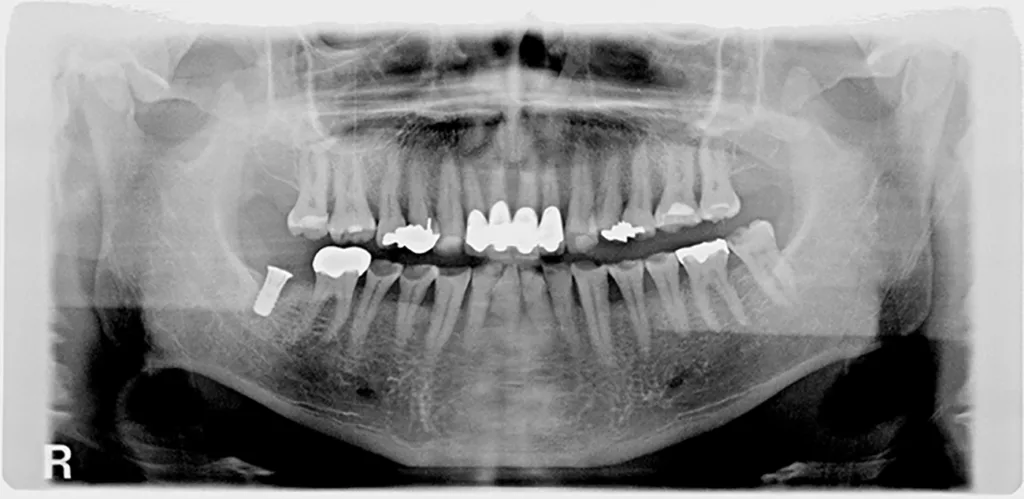

Die OPT-Aufnahmen zeigen keinen Anhalt auf nicht zahnverursachte Prozesse, dafür einen leichten bis mäßigen horizontalen und vertikalen Knochenabbau im Oberkieferseitenzahnbereich und generalisiert im Unterkiefer sowie einen periimplantären Knochenabbau in Regio 47 (Abb. 2). Die Zahnhartsubstanzdefekte imponieren als halbmondförmige Aufhellungen im Okklusalbereich von den Zähnen 37, 35, 34, 44 und 45. Es zeigen sich ebenso Aufhellungen im Approximalbereich mesial 24, distal 43 und mesial 37 (Abb. 4 und 5).

Parodontale Gesundheit bei Attachmentverlust, Bruxismus, Erosion. Abbildung 1 sowie 6 bis 9 zeigen den Anfangsbefund als intraoralen Fotostatus.*